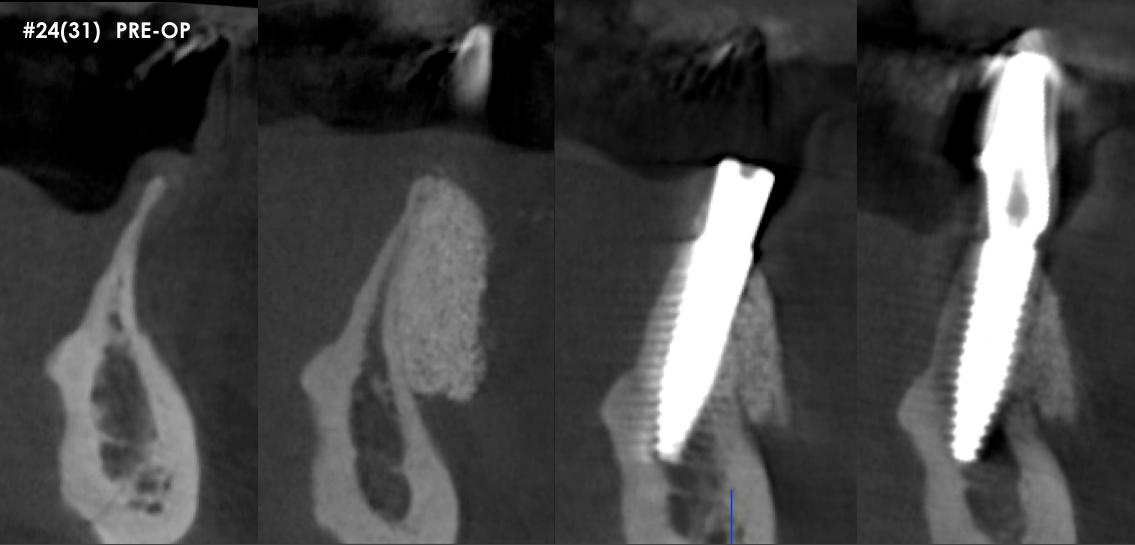

Vertical and horizontal augmentation of thin mandibular posterior ridge. The patient sought a minimally invasive approach, having previously declined treatment proposals that included hip and block grafts.

S.M.A.R.T. Vertical and horizontal mandibular ridge augmentation.  Once again, no flaps, tenting screws or membranes were used. Compared to traditional GBR/block/hip grafting techniques...this was a 45 minute in-office procedure, with less pain, less swelling and fewer potential complications. Implants will be placed following a 6-month healing period.